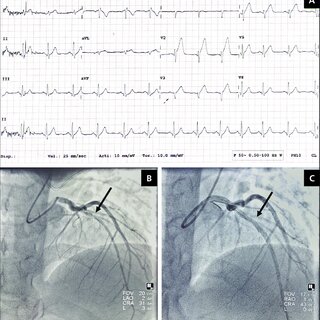

변이형 협심증 진단

우선 의사의 증상과 병력, 위험요인등을 문진한뒤 EKG(심전도검사), 관상동맥조영술, 심장에 부하를 주는 테스트, 혈액검사 등으로 진단을 하게 됩니다.